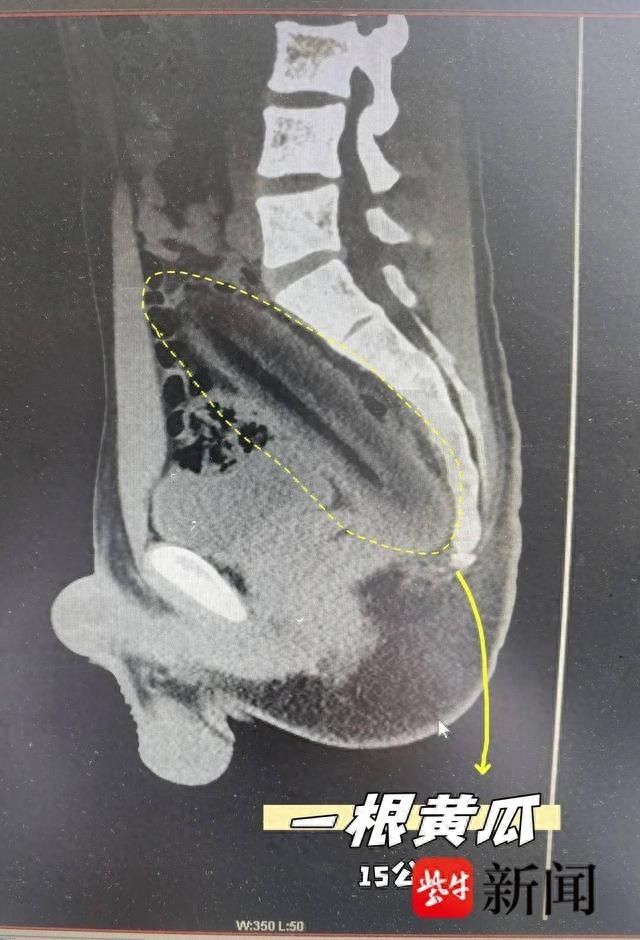

男子为刺激排便将15厘米黄瓜塞进肛门图像显示黄瓜保留在体内。由于长期的便秘,扬州的一个年轻人王认为黄瓜可以通过他的肛门激发肠道运动。 3月27日,他尝试了此程序,但黄瓜不小心滑入直肠,无法移开,导致腹部伸展难以忍受,最终去了医院的急诊室。王小王通常会迟到玩游戏,更喜欢诸如炸鸡和米蛋糕之类的粘合剂食品,并且长期患有便秘。突然一时兴起,他决定使用这种方法,但出乎意料的是,黄瓜已经滑入直肠,不能单独服用。进入后,CT报告显示直肠和乙状结肠区域的外国体阴影长长,直径为41mm,长度为152mm。杨苏传统医学医院厌氧部部门部门主任Chen Xiao,迅速器官iz iz团队进行行动。随着一系列的非侵入性手术,例如麻醉和括约肌松弛,扩大肛门,并用软镊子夹紧,黄瓜可以成功去除15厘米。整个过程仅持续20分钟。手术后,王王表示遗憾,并承诺将来不要轻松尝试任何民间补救措施。专家提醒您,当您不舒服时,您应该尽快去普通医院接受治疗,并且不相信在线补救措施。